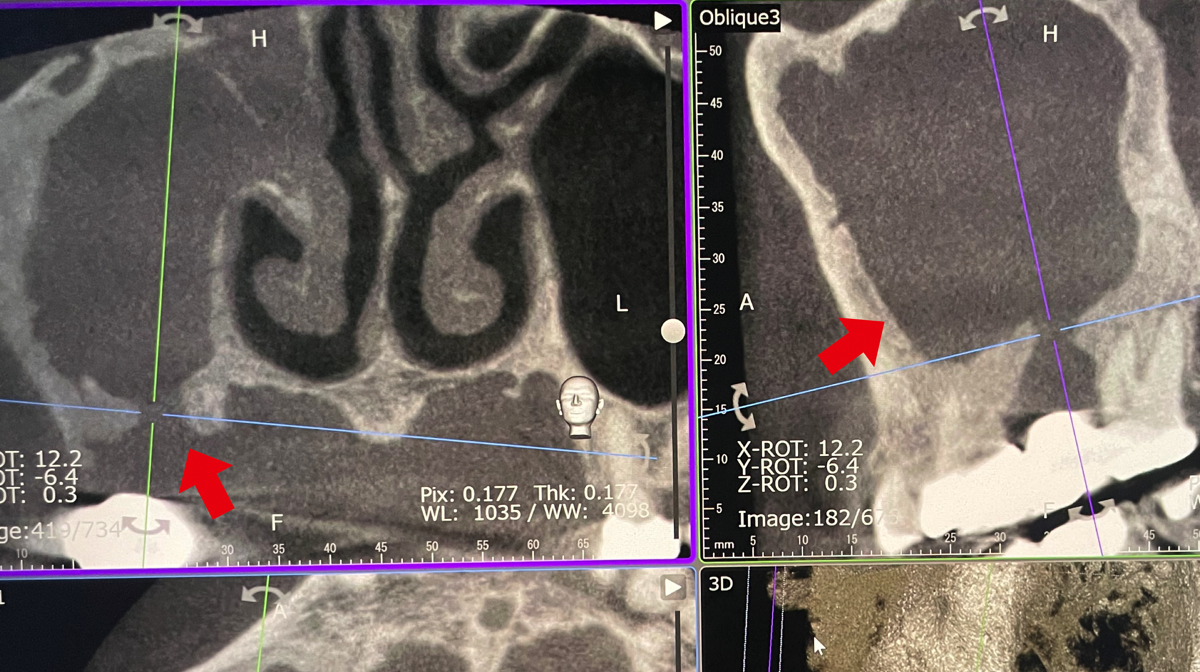

上あごの奥歯のむし歯に継発して歯根が感染を起こすと、鼻汁や鼻漏さえ伴う歯性上顎洞炎を生じることがあります。これも鼻が悪いからと放置して慢性化している人が多いように感じます。従来の歯科用エックス線撮影で左右の上顎洞の影の違いから見つかることもありますが、歯科用CT撮影ではより明確に上顎洞の状況を観察することができます。歯科での治療が中心になりますが、耳鼻科医との連携が必要になることもあります。

一方、同じ人の歯科用3次元CT撮影画像では上顎洞に不透過像が観察され、底の部分の骨欠損も明瞭に確認できた(自院撮影)。